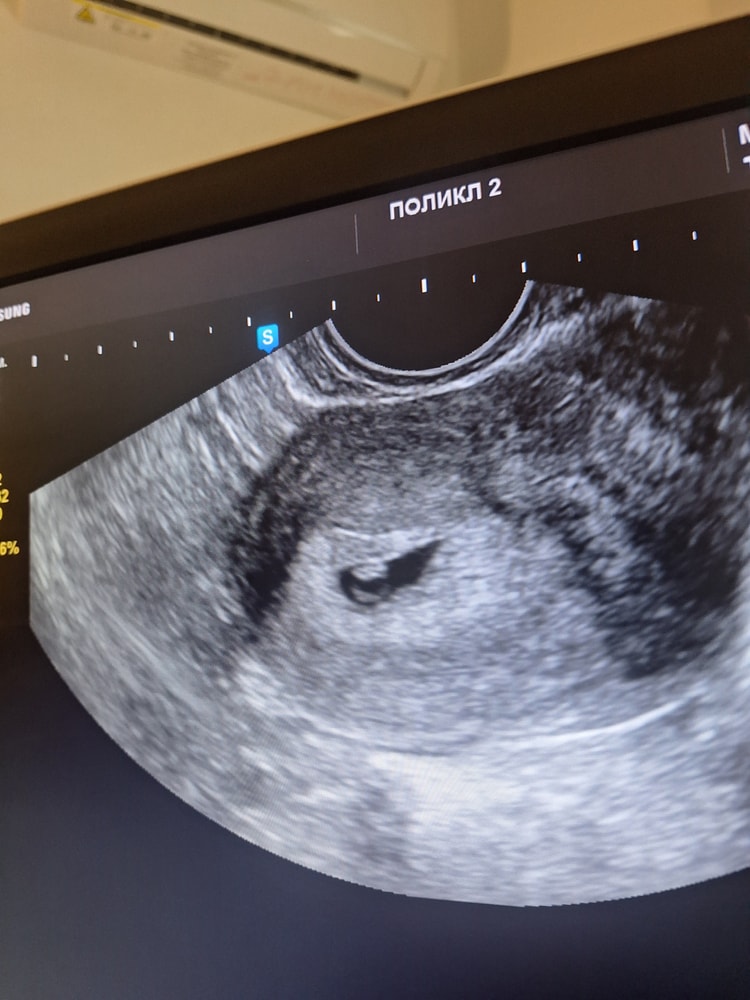

Креветочка наша на месте, дали послушать сердечко 🥰 Расплакалась 🥹 По месячным срок сегодня 5н 6д, по УЗИ - 6-7 недель ❤️ Запомнила только КТР 4.6мм и ЧСС 126 уд/мин 😃 (в протоколе УЗИ врач написала почему то 143 уд/мин, хотя устно мне сказала 126).

И таки нашли ретрохориальную гематому. Сказали, что уже заживающая и небольшая. Я ума не приложу откуда (грешу на миому). Кстати, миома так же 3 см, пока не увеличивается, будем наблюдать.

Врач УЗИ меня поздравила, сказала, что малыш развивается как полагается и все у нас хорошо, а гематома эта не страшна и все будет отлично 🙂 Лечащий врач оставила меня до пятницы понаблюдать как я без транексама буду. Я что то боюсь, что гематома эта выходить кровью опять начнет...